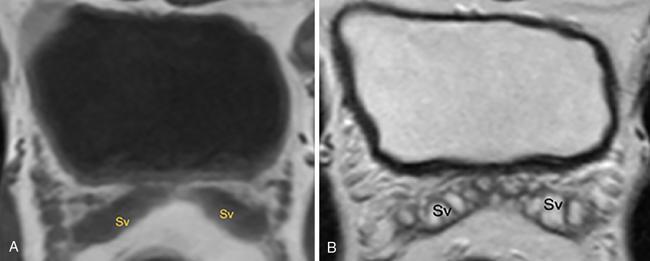

IMAGING ANATOMY OF MALE REPRODUCTIVE SYSTEM Ganesh Rajagopal The male reproductive system is formed by testes, ejaculatory ducts, seminal vesicles (SVs), prostate and penis. Various diagnostic imaging modalities like ultrasound (US), computed tomography (CT), magnetic resonance imaging (MRI) and positron emission tomography (PET) are helpful in the diagnostic evaluation of male reproductive system. Various indications for imaging may include acute scrotum (testicular torsion, trauma and epididymo-orchitis), scrotal swelling (hydrocele, spermatocele, idiopathic scrotal wall oedema and scrotal abscess) and infertility. US and MRI are the commonly used imaging modalities in male reproductive system which complement each other. CT is not very useful due to poor contrast resolution. Ultrasound imaging (US) with a high-frequency linear (7.5–10 MHz) transducer probe has become the imaging modality of choice for scrotal evaluation. Scrotal US is an excellent imaging modality as it can demonstrate abnormalities in testis as well as in paratesticular structures. Scrotal wall is formed by the skin, superficial fascia, dartos muscle, the external spermatic fascia, cremasteric fascia and the internal spermatic fascia. The scrotum is divided into two cavities by a median raphe. This multilayered scrotal wall is poorly delineated in US and MRI, it is typically hypointense on both T1- and T2-weighted images. Testes are paired organs, located normally in scrotal sac, suspended by the spermatic cords. Each testis is examined in orthogonal transverse and longitudinal planes, with both grey scale and colour Doppler modes, to assess its volume and blood flow. Volume of testis is calculated by length × height × width × 0.71. A total volume (both testes) of >30 mL and a single testicular volume of 12–15 mL is generally considered normal for adults. Testes are supplied by the testicular arteries, which arise from the aorta and enter the spermatic cord at deep inguinal ring to reach the upper pole of testis. Pampiniform plexus of veins surrounds the testis and appears as a serpiginous tubular structure posterior to it, measuring >2–3 mm in diameter. Testes are oval shaped, with homogeneous echotexture on grey scale US. Along with the epididymis, they are surrounded by an echogenic capsule, known as the tunica albuginea. Tunica albuginea is covered by tunica vaginalis, which is a remnant of the processus vaginalis and both represent closed sac of peritoneum with two layers. This tunica albuginea is seen extending into posteromedial testis and form the mediastinum testis (Fig. 11.2.1.1), which consists of ducts, nerves and blood vessels. The mediastinum testis is seen as a thin echogenic band. Rete testis is formed by the convergence of seminiferous tubules, seen as a hypoechoic area adjacent to mediastinum testes. The epididymis is a comma-shaped, elongated structure placed at the posterior border of the testis, which drains the efferent ductules (Fig. 11.2.1.2). It has head, body and tail. The head overlies the superior pole of the testis and is isoechoic or slightly hyperechoic whereas, the body and tail are located behind and along the inferior pole and are usually isoechoic. The tail of the epididymis continues into vas deferens (VD), which along with the nerves, lymphatic and vascular structures, forms the spermatic cord (Fig. 11.2.1.3). The spermatic cord appears as an echogenic band in the inguinal canal. The normal adult testis is a homogeneous oval structure that appears hyperintense on T2-weighted sequences and hypointense–isointense on T1-weighted images (Fig. 11.2.1.4). The tunica which surrounds the testis is hypointense T1- and T2-weighted sequences. Epididymis is isointense on T1-weighted images but hypointense on T2-weighted images compared to testis (Fig. 11.2.1.5). Both testicles and epididymis enhance after intravenous administration of gadolinium (Gd) MR contrast agents. Prostate, though visualized by transabdominal scan is better assessed by transrectal high frequency (7.5–10 MHz) ultrasound transducer (TRUS) with patient in left lateral decubitus position. The prostate gland is divided into the anterior fibromuscular stroma (devoid of glandular tissue), transition zone, central zone, periurethral zone and peripheral zone. The base of the prostate is located superiorly and contiguous with the bladder neck whereas, the apex of the prostate is located at the inferior aspect continuous with the striated muscles of the urethral sphincter. The neurovascular bundle is seen to course near the posterolateral aspect of prostate, which is a preferential route of tumour spread. The prostate appears as a cone-shaped organ and shows uniform low echogenicity (Fig. 11.2.1.6). The outer gland (central and peripheral zones) is generally more echogenic than the inner gland. The transition and central zones of the prostate have similar MR signal intensity and cannot be differentiated, hence, are collectively referred as the central gland. On T2-weighted MR images, the normal peripheral zone is homogeneously hyperintense, whereas the central gland tissue is typically hypointense or isointense compared to the skeletal muscle (Fig. 11.2.1.7). The capsule and the anterior fibromuscular stroma appear hypointense on T2-weighted MR images. The SVs are seen as septate tubular cystic structures, appearing uniformly anechoic in US, above the prostate with distal portion of VD is seen medial to it. The duct of SV and VD joins to form the ejaculatory duct, which drains into the prostatic urethra via verumontanum. SVs show ‘bow-tie’ appearance in transversal scans, and a club or tennis-racket shape in longitudinal scans (Fig. 11.2.1.8). On MR, SVs are seen as elongated fluid-containing structures with thin septa, which is hypointense on T1 and hyperintense on T2-weighted MR images (Fig. 11.2.1.9). The VD is seen as a tubular structure with low signal intensity in both T1- and T2-weighted images, on either side. The dilated distal portion of VD (ampulla), appears hyperintense on T2-weighted images, similar to that of the SV due to the fluid content (Fig. 11.2.1.10). The penis, being a superficial organ, is usually examined with US, although MRI is reserved as problem solving modality. The penile body contains two paired muscles – corpora cavernosa and a corpus spongiosum. The former performs as a main erectile body while the latter contains the penile urethra (Fig. 11.2.1.11). Dartos fascia forms the outer layer and the Buck fascia forms the inner layer, which contain the deep dorsal vein (DDV) and a paired dorsal neurovascular bundle. The corpus spongiosum and corpora cavernosa are of high signal intensities on T2-weighted MR images and intermediate-low signals on T1-weighted MR images. The tunica albuginea being a fibrous sheath, surrounds all the three muscles, is hypointense on all sequences (Fig. 11.2.1.12). IMAGING ANATOMY OF FEMALE REPRODUCTIVE SYSTEM Saranya The female reproductive system comprises of uterus, cervix, fallopian tubes, ovaries, vagina and vulva. Ultrasonography (transabdominal and transvaginal) is the primary imaging modality of choice for imaging the female pelvis. Computed tomography (CT) is less often used for pelvic imaging. It provides a quick and systematic overview with coverage of the abdomen in the same session. Hence, CT is well suited for staging pelvic cancers and for imaging gynaecologic and nongynaecologic diseases presenting with acute abdominal pain. Pelvic anatomy is well demonstrated by magnetic resonance imaging (MRI). The contrast resolution of T2-weighted images form the basis for superb tissue characterization of MRI. Uterus is a thick-walled fibromuscular organ composed of myometrium and endometrium. It has two major divisions, namely, the body (corpus) and cervix. The fundus lies above the ostia of fallopian tubes. The normal uterus measures between 5 and 9 cm in length and is in an anteverted position, in relation to the urinary bladder. The myometrium shows three layers on USG, a compacted thin, hypoechoic inner layer forms subendometrial halo, a thicker, homogenously echogenic middle layer and a thinner, hypoechoic outer layer (peripheral to arcuate vessels). The appearance of the endometrium varies with the phase of the menstrual cycle. It appears as a thin echogenic line early in the proliferative phase and shows hypoechoic thickening (4–8 mm) as proliferative phase progresses. It shows a triple layer (sandwich or trilaminar) appearance in the mid cycle and may measure up to 12–16 mm. During secretory phase after ovulation, the layers are seen hyperechoic due to the increasing complexity of glandular structure and secretions (Fig. 11.2.2.1). Postmenopausally, the endometrium decreases in thickness. Endometrial thickness of 5 mm is taken as cut-off. Women on hormonal therapy acceptable endometrial thickness is up to 8 mm. Three-dimensional US permits multiple views to be reconstructed from a single sweep through the uterus. Sonohysterogram is the study of choice for detailed evaluation of the endometrial cavity pathologies. The cervix begins at the inferior narrowing of the uterus (isthmus) at the internal os, which is identified by the entrance of uterine vessels. It has supravaginal and vaginal portions. It is 3–4 cm long and shortens after childbirth. In premenarche women, cervix is larger than corpus, forming approximately 2/3 of the uterine mass. During menarche, there is preferential growth of the corpus and in nulliparous women, corpus and cervix are roughly equal, whereas in parous woman, corpus forms approximately 2/3 of the uterine mass. Uterus is an extraperitoneal organ. The peritoneum extends over urinary bladder dome to anterior uterus, forming anterior cul-de-sac (vesicouterine pouch) and posteriorly, the peritoneum extends more inferiorly to the upper portion of vagina, forming the posterior cul-de-sac (pouch of Douglas, rectouterine pouch), which forms the most dependent portion of the female pelvis. Supporting ligaments of the uterus comprise mainly of broad ligaments, which extend laterally to the pelvic wall and round ligaments, which arise from uterine cornu near fallopian tubes to course anteriorly, pass through the inguinal canal to insert on the labia majora. Connective tissue thickening at the base of the broad ligament forms the uterosacral ligaments posteriorly, cardinal ligaments laterally and vesicouterine ligaments anteriorly. CT examination displays the uterus as a triangular or ovoid soft tissue structure behind the urinary bladder (Fig. 11.2.2.2). Following the administration of intravenous contrast, there is enhancement of myometrium that helps to delineate the endometrium. The vagina, cervix and corpus can be differentiated by morphological characteristics and enhancement pattern. The uterine corpus is typically triangular, whereas cervix is more rounded. The vagina has an appearance of flat rectangle at the level of fornix. The broad ligament and round ligaments are seen coursing laterally and anteriorly, respectively. The main source of vascular supply to uterus is from the uterine arteries. The uterine arteries pass within the broad ligament to enter the uterus, adjacent to the lateral fornices. The uterine artery passes over the ureter at the level of the cervix. Then it courses superiorly, along the lateral margin of the uterus and anastomoses with the ovarian artery. Uterine arteries give rise to arcuate arteries, which run in the outer third of myometrium. Radial arteries extend through the myometrium, which terminate as spiral arteries in the endometrium. The venous system parallels the arterial system, forms a complex venous network in the parametrium and drains to the iliac veins. Middle and lower thirds of the uterus are drained by obturator, parametrial and paracervical lymph nodes. Lymphatic drainage from the upper corpus and fundus goes to the common iliac and paraaortic lymph nodes. MRI provides a more comprehensive view of the uterine anatomy. On MRI, the uterus and cervix show uniform low to intermediate signal on T1-weighted images. On T2-weighted images, uterus shows three distinct zones, namely high signal endometrium, low signal junctional zone and intermediate signal myometrium (Fig. 11.2.2.3). The normal thickness of the junctional zone varies from 2 to 8 mm. A thickness of 9 to 12 mm is equivocal and greater than 12 mm is abnormal. Both endometrium and junctional zone become thin with oral contraceptive intake. Endometrial atrophies and the junctional zone is absent in postmenopausal women. The endocervical canal shows high signal on T2-weighted images, whereas cervical stroma shows low signal, contiguous with the junctional zone. An outer layer of intermediate signal smooth muscle is present. Nabothian cysts representing obstructed, mucous secreting glands are commonly seen as low signal on T1-weighted images and high signal on T2-weighted images. Parametrium shows low to intermediate signal intensity on T1-weighted images and variable signal intensity on T2-weighted images. The round ligaments and uterosacral ligaments show low signal intensity, cardinal ligaments and associated venous plexuses show high signal intensity on T2-weighted images. Ovaries are located posterolateral to the body of the uterus between the uterus and the pelvic sidewall. The internal iliac vessels lie immediately posterior to the ovary. Exact position is variable due to the laxity in the ligaments, parity, uterine size and position. On USG, medulla of the ovaries is mildly hyperechoic compared to the hypoechoic cortex. Developing follicles appear anechoic (Fig. 11.2.2.4). Corpus luteum may have a thick, echogenic ring and haemorrhage is common.